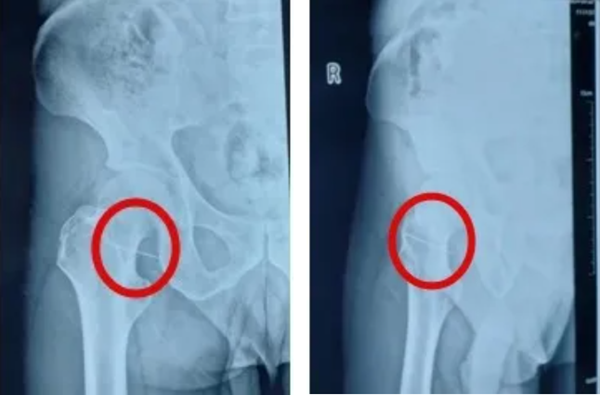

居然发现髋部内有一针状异物

CT结果显示

针的位置非常接近股动脉

情况十分危急

术中发现针头距离股动脉仅1cm

若再进一步,可能造成无法挽回的严重后果